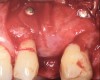

Fig 12. Treatment of peri-implantitis: peri-implant mucosal inflammation associated with plaque and calculus accumulation.

Figure 12

Fig 13. Radiograph depicting crestal bone loss around mandibular implants.

Figure 13

Fig 14. After removing the prosthesis, presence of peri-implant plaque and calculus.

Figure 14